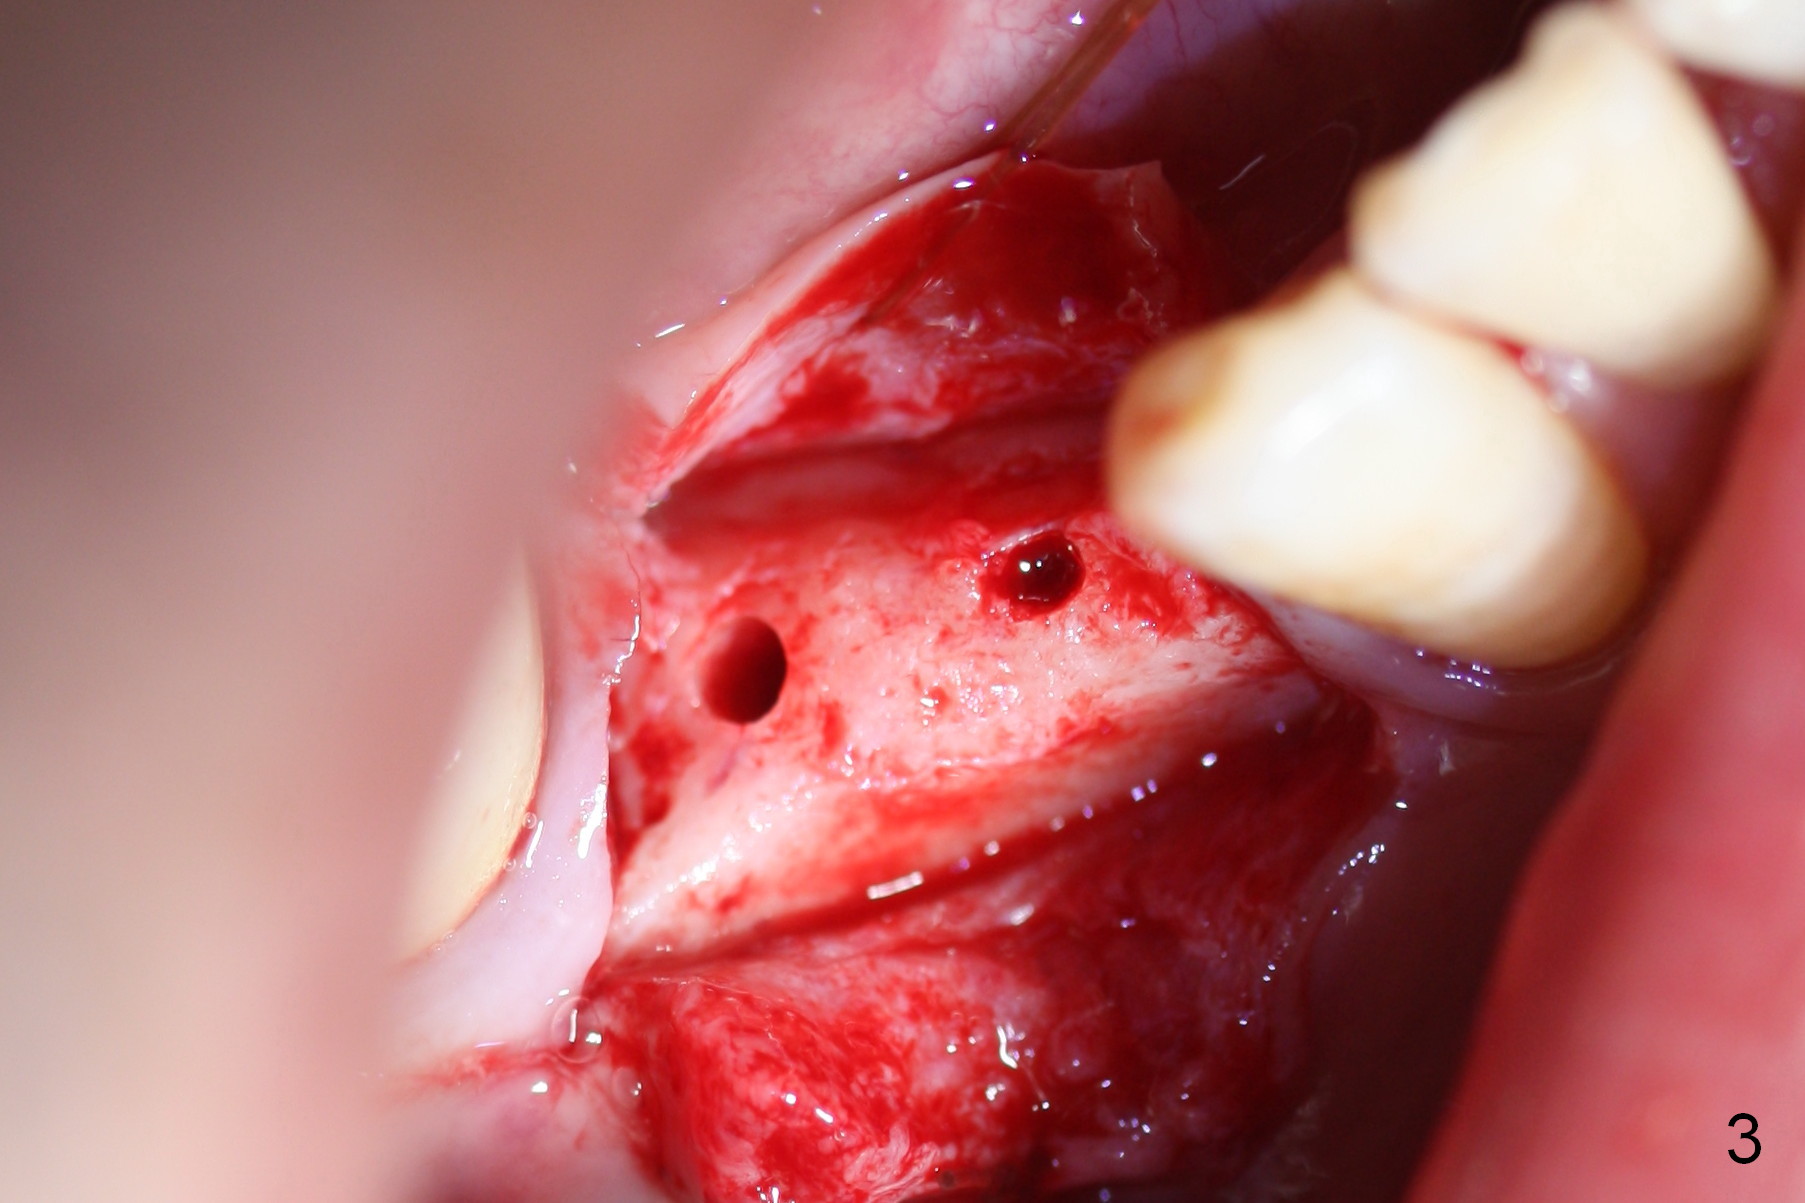

The patient has lost several teeth, which are replaced by removable partial dentures. He wants to have implants in the lower right first because of loss of a buccal clasp over the tooth #30 (Fig.1). When the lower partial is removed, a narrow soft tissue band is visible in the edentulous area. The hard tissue ridge is approximately 3 and 5 mm buccolingually at the sites of #28 and 29, respectively (Fig.3 after initial osteotomy). To place 2 adjoining implants at the same level, the treatment plan is modified: a 3 mm 1-piece implant will be placed at #28, while the plan at #29 remains the same: a 4.5 mm 2-piece implant.

The 1st intraop PA taken after initial osteotomy at the depth of 12 mm shows that the mental loop (Fig.4 red dashed line) appears to be more superior than what is expected from CBCT study; while the apical end of the osteotomy at #28 is going to be moved mesially (>), that at #29 distally (<). Both implants (3x14 and 4.5x12 mm) are placed with insertion torque 56 Ncm (Fig.5). After placement of a 5.8x4(2) mm abutment at #29, an immediate provisional is fabricated and cemented (Fig.6 P). The partial is modified and the left portion is seated (Fig.6 <). The patient is pleased with the change: from removable to fixed appliance. There is no paresthesia postop.